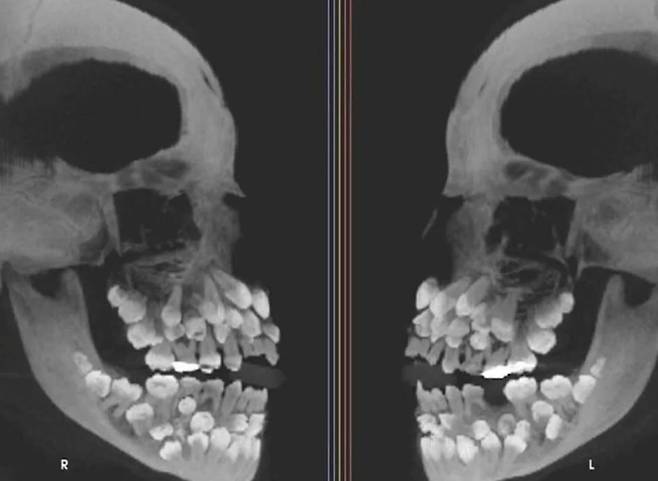

그러나 엑스레이 촬영 결과, 그녀의 잇몸 속엔 무려 81개의 치아가 숨어 있었고, 이 사실은 의료진은 물론 국제 학계까지 충격에 빠뜨렸습니다.

보통 성인은 사랑니를 포함해 32개의 치아를 갖고 있지만, 이 소녀는 유치 18개, 영구치 32개, 그리고 과잉치 31개까지 총 81개의 치아를 보유하고 있었습니다.

이러한 상태는 ‘다발성 과잉치증’으로 불리며, 보통은 1~2개의 과잉치만 나타나는 반면, 30개가 넘는 경우는 세계적으로도 매우 희귀합니다.